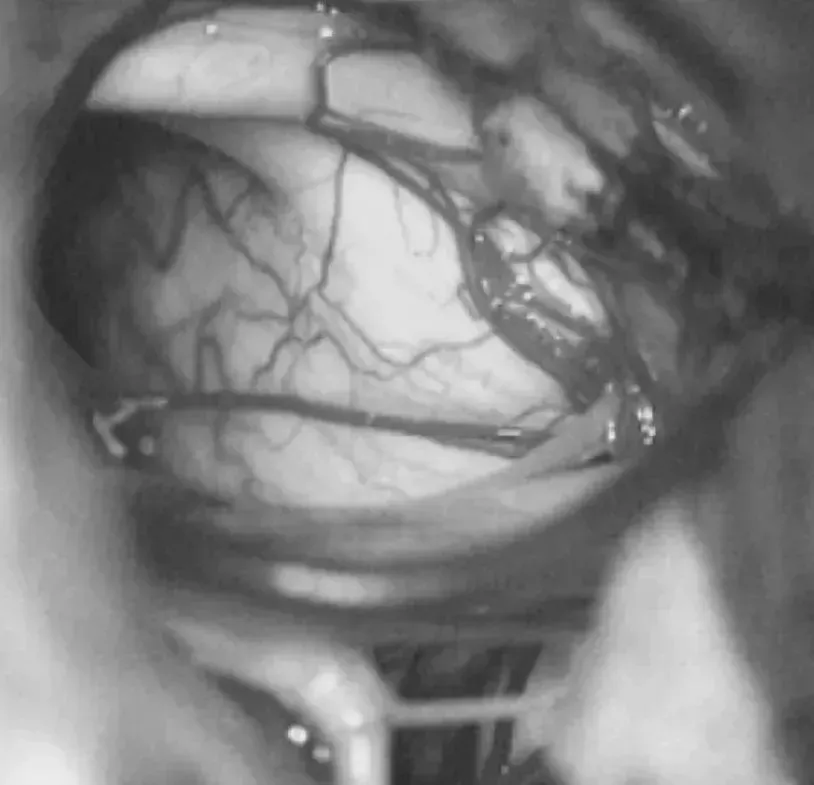

手术当天,整个团队严阵以待。这场手术的每一步,都像是在“刀尖上跳舞”:巴教授选择“乙状窦后入路”开颅——这一入路能绕开重要血管神经,直达脑干病变区域,最大程度减少对正常脑组织的损伤。

术中全程开启电生理监测,在高倍显微镜下,教授一点点分离病变与正常脑干组织,避开缠绕的颅神经,最终将海绵状血管瘤完整取出。

术中开颅、切开硬膜后,暴露脑干,用电生理监测术中探测核团所在。